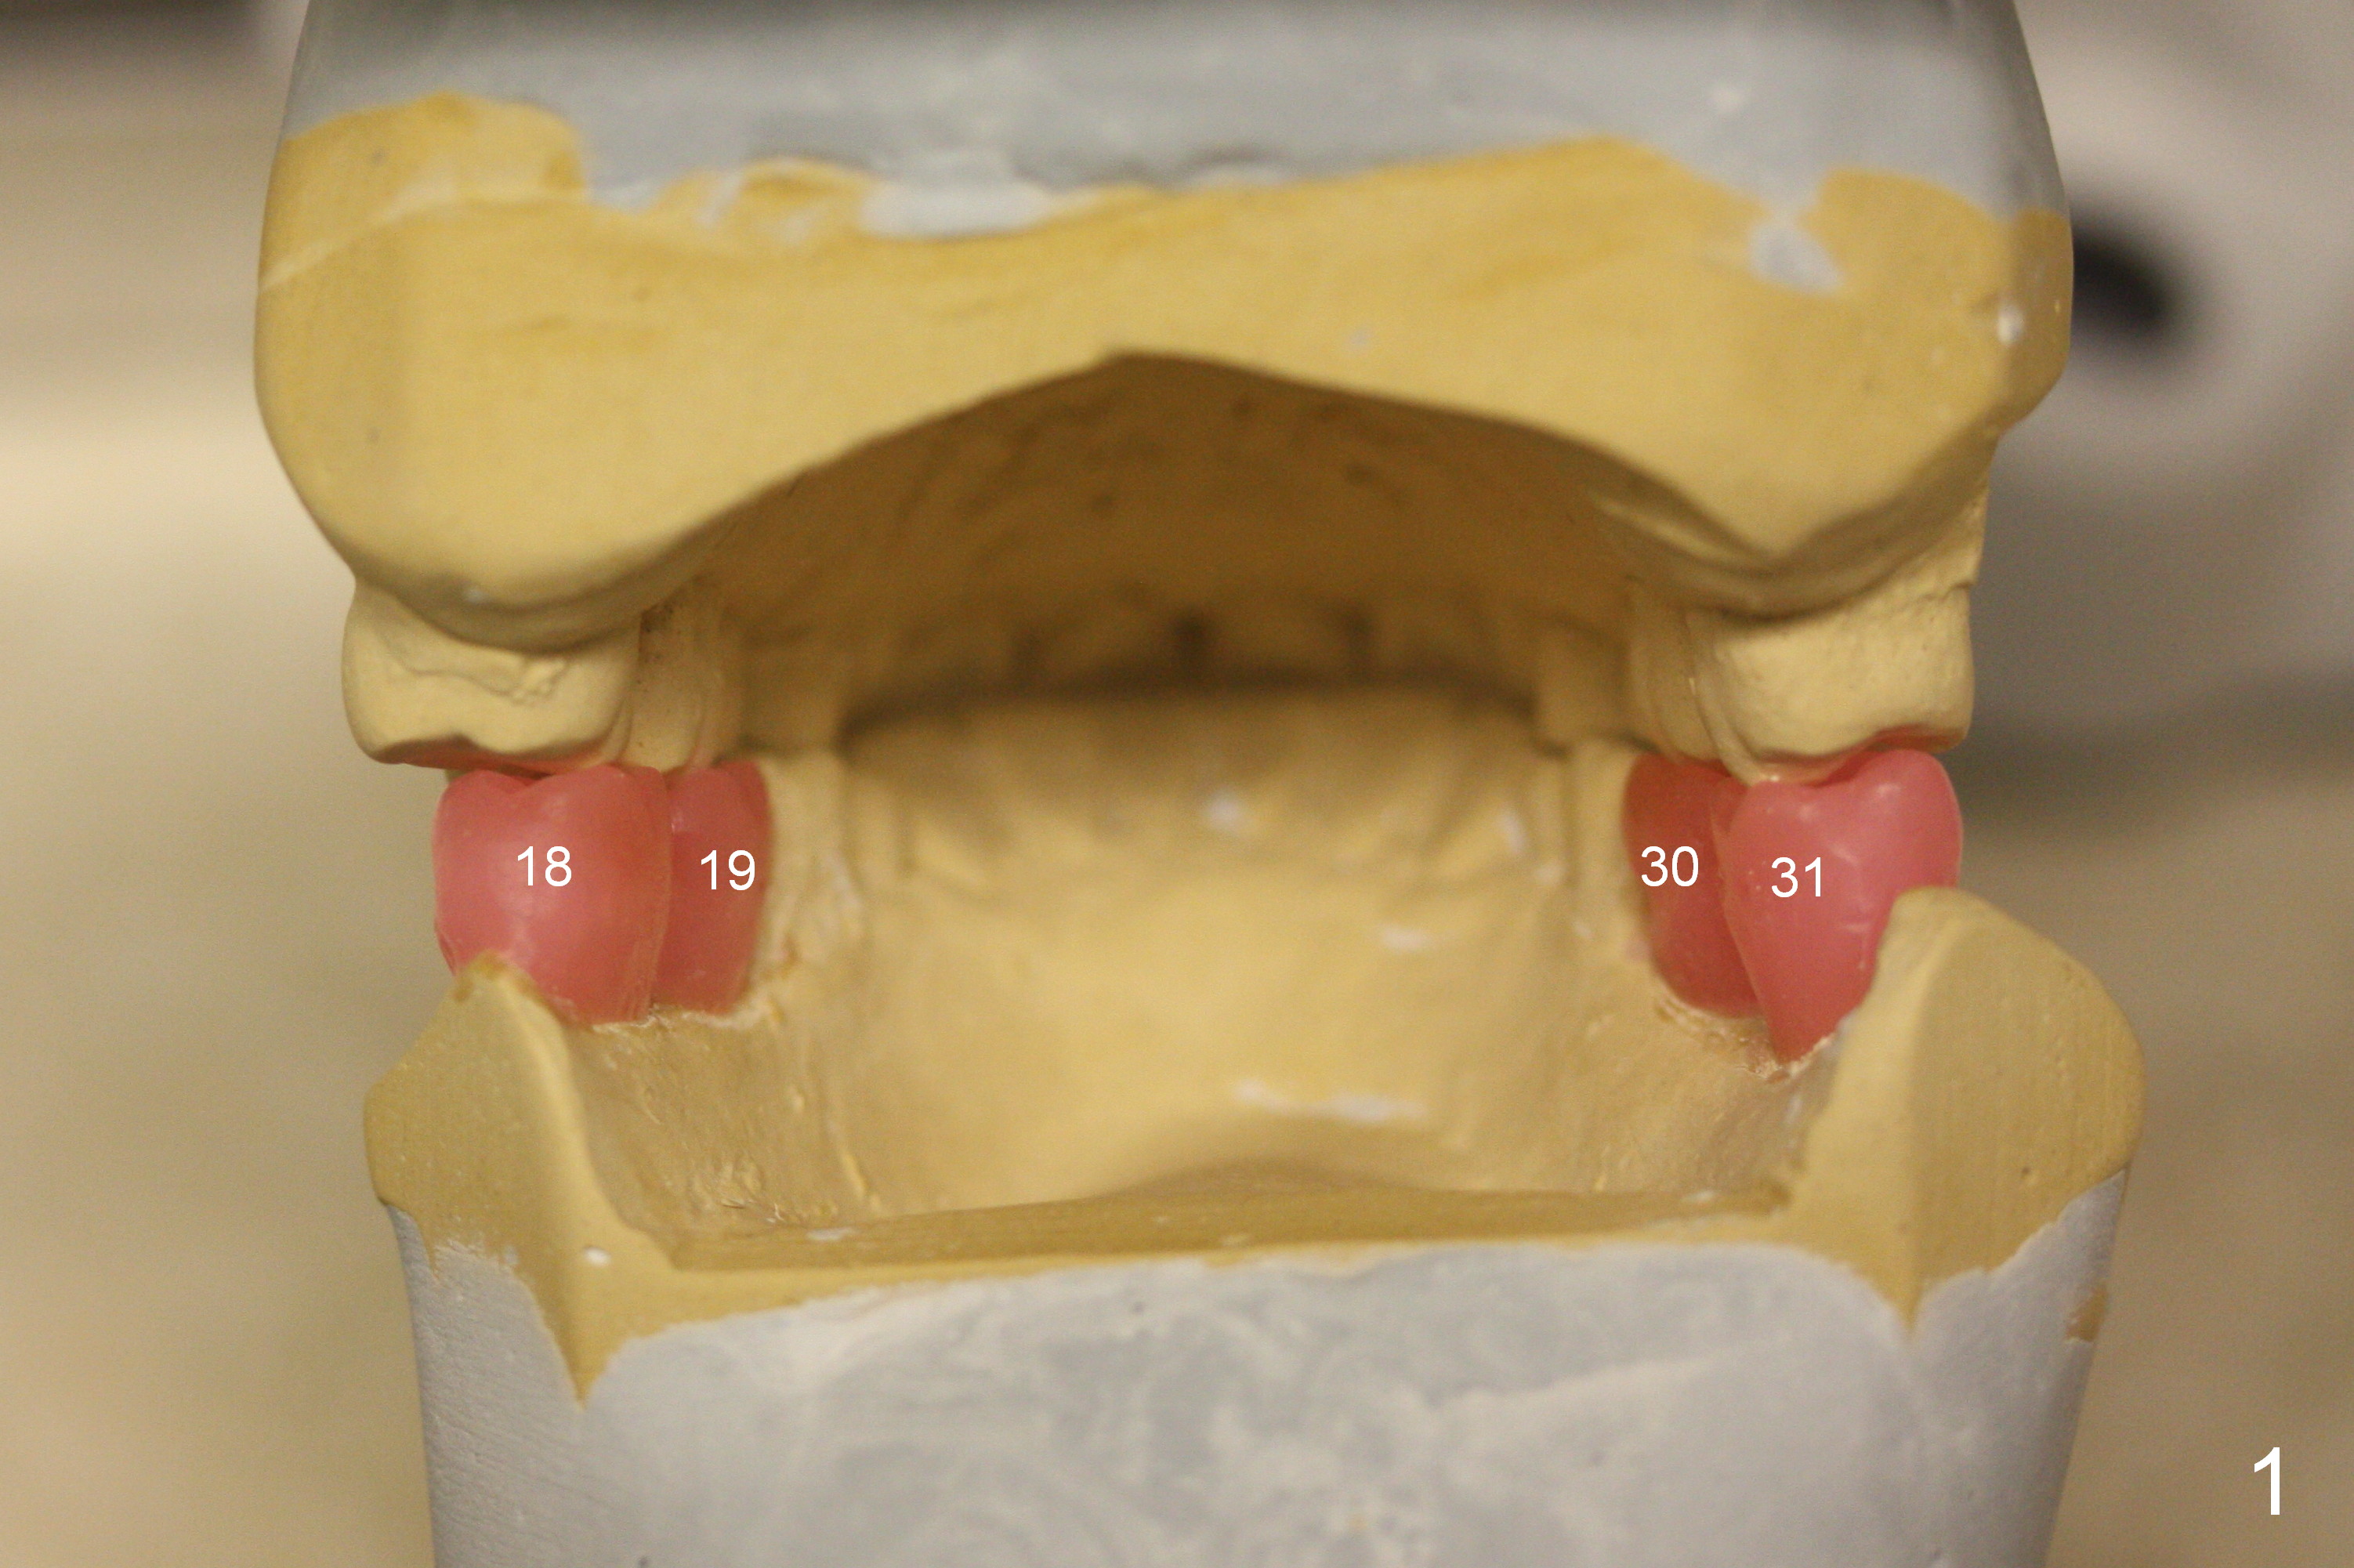

A 64-year-old man has lost 4 molars (Fig.1 posterior view of mounted casts) and is eager to have them back. Implants will be placed at #18 and 19 first (Fig.2). Use surgical stent and starter drill to initiate osteotomies through the gingiva. An incision will be made next. Adjust buccolingual position of the osteotomies. Depth will be 10 and 12 mm at #18 and 19, respectively. Take postop panoramic X-ray for #30 and 31 implant design.

In fact, initial depth for #18 and 19 is 12 mm, quite close to the Inferior Alveolar Canal at #18 (Fig.3 (red dashed line: the superior border of the former). By mistake, the implant at #18 is placed a little deeper than necessary, since the buccal bone is inferior to the lingual one (Fig.4; 5.3x12 mm vs. 5.0x12 mm for #19). As planned, panoramic X-ray is taken immediately postop. Bone height at the 2nd molar decreases drastically as compared to that of the 1st molar, especially on the right side (Fig.5 (abutments: 6.8x5(2) mm for #19, 7.8x5(3) for #18, respectively)). For #30,31 implant placement, initial depth will be 10 and 8 mm, respectively. Follow it faithfully. The implant at #31 could be as large as 5.9 or 6.4 mm to compensate for the length.